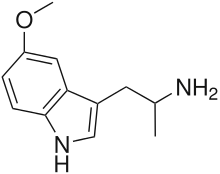

List of substituted α-alkyltryptamines

α-Alkyltryptamines are a group of substituted tryptamines which possess an alkyl group, such as a methyl or ethyl group, attached at the alpha carbon, and in most cases no substitution on the amine nitrogen.[17][18][19] α-Alkylation of tryptamine makes it much more metabolically stable and resistant to degradation by monoamine oxidase, resulting in increased potency and greatly lengthened half-life.[19] This is analogous to α-methylation of phenethylamine into amphetamine.[19]

5-MeO-αMT | 1-(5-methoxy-1H-indol-3-yl)propan-2-amine | 1137-04-8 |